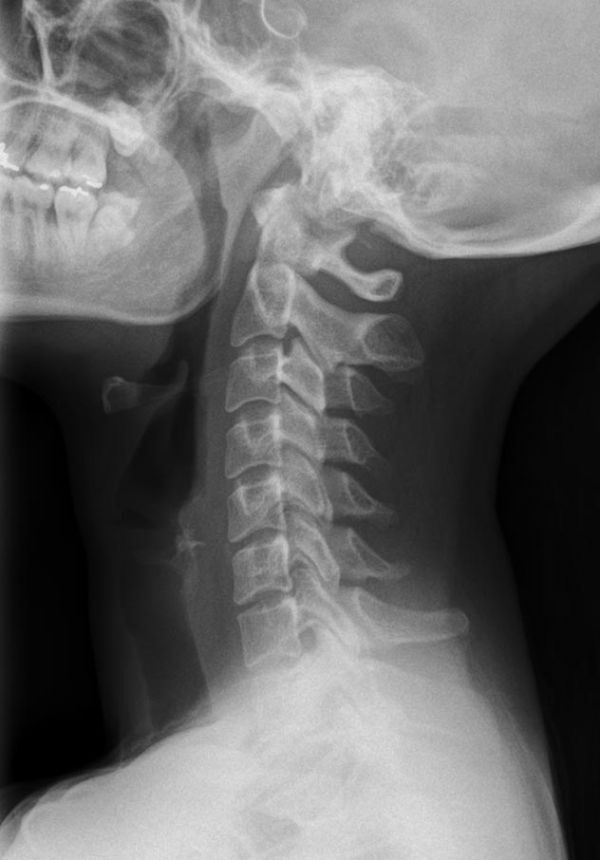

Konventionelles Röntgen

Der Begriff Röntgen, oder auch Röntgendiagnostik bezeichnet ein Verfahren in der Radiologie, bei dem von einer Röntgenröhre elektromagnetische Wellen (Röntgenstrahlen) durch die zu untersuchende Körperregion des Patienten gesendet werden. Je nach Dichte der Gewebeart des Körpers (z.B. Knochen oder Lunge) werden die Röntgenstrahlen im Körper unterschiedlich stark abgeschwächt. Ein digitaler Detektor empfängt dann die Röntgenstrahlen, die in abgeschwächter Form den Körper wieder verlassen haben. Daraus wird das Röntgenbild erzeugt.

Die zu untersuchenden Anteile des Körpers werden meistens

in 2 unterschiedlichen Projektionsebenen dargestellt.

In einigen Körperregionen sind spezielle Zielaufnahmen notwendig.